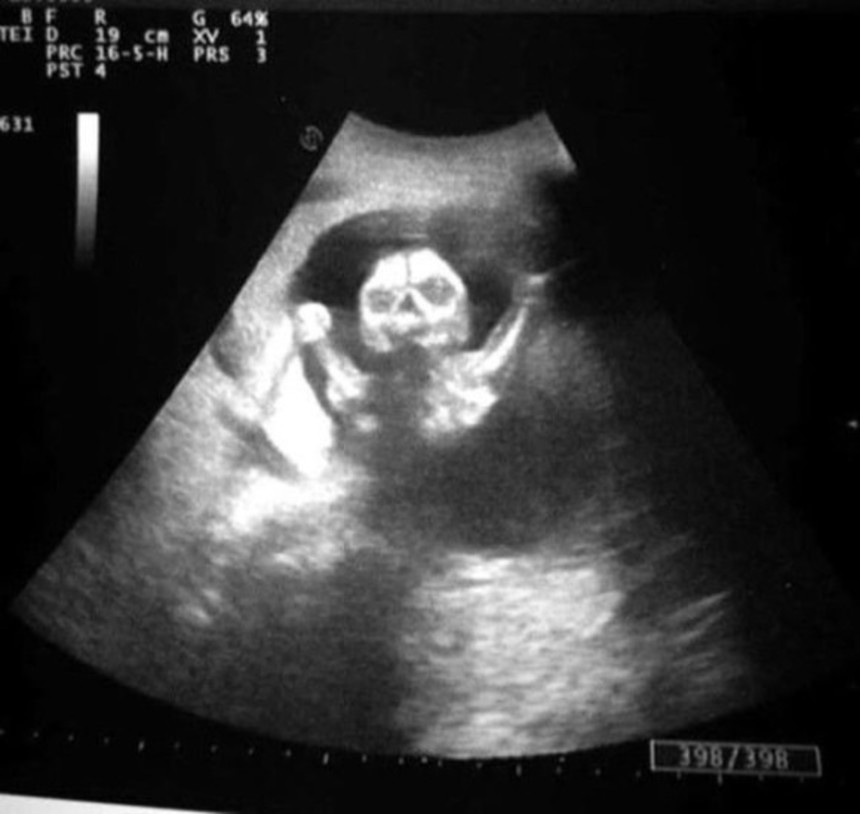

人間の脳は、3つの点が集まった図形を人の顔と見るようにプログラムされているようにできている。これはシミュラクラ現象と呼ばれるものなのだが、モノクロで撮影された胎児の超音波写真は、見方によってはホラーとしか言えない悪夢的光景が潜んでいるようなんだ。

これらの超音波写真は、親御さんがネット上で公開したもので、見方によっては腹にやばいものが宿っているように見えるものだ。

実際には断面図だから骸骨っぽくなっちゃうんだよね